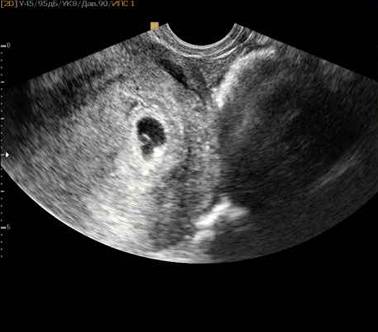

- УЗИ. При исследовании уже можно увидеть зародыш (точку в полости матки).

УЗ-исследование на раннем сроке может точно показать место крепления яйцеклетки и вовремя распознать внематочную беременность. Если пропустить симптомы, растущее яйцо может разорвать маточную трубу, что очень опасно. При нормальном течении беременности УЗИ не нужно. К концу четвертой недели можно определить только факт крепления плодного яйца на стенке матки. Эмбрион еще слишком мал, и провести диагностику развития ребенка не получится. Размер малыша на четвертой неделе около 1 мм и вес 0,5 г.

Зародыш сейчас напоминает маковое зернышко: в нем не больше 1 мм и 0,5 грамм. На снимке УЗИ можно различить лишь небольшое темное пятнышко. Но несмотря на скромные размеры в нем уже заложены основы для развития всех органов и систем.

- УЗИ – в конце 4 акушерской недели на высокоточном оборудовании можно увидеть утолщенный эндометрий и черную точку на нём – прикрепившийся эмбрион.

УЗИ на 4 неделе по эмбриональному методу проводят при помощи трансвагинального датчика. На этом сроке имеющаяся беременность хорошо различима.

Что можно увидеть:

- Расширенные кровеносные сосуды эндометрия, дающие эмбриону возможность питаться;

- Плодный мешок в виде черного кружка диаметром в несколько миллиметров;

- Желточный мешок в виде маленького колечка диаметром 2-3 мм.

Сам эмбрион будет возможно различить на желточном мешке ещё через неделю. Ультразвуковое исследование на этом сроке беременности проводят исключительно по медицинским показаниям – исключение пузырного заноса, внематочной беременности.